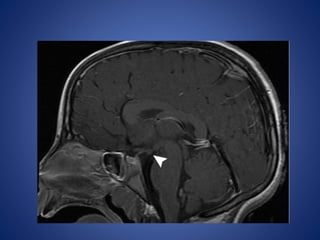

Hypothalamic Hamartoma

Hypothalamic hamartoma is the lesion most commonly associated

with CPP, being implicated in up to 60% of cases.

Hypothalamic hamartomas may be either

• sessile (intrahypothalamic) or

• pedunculated (parahypothalamic).

Imaging Features.—

Sessile hypothalamic hamartomas may expand the hypothalamus.

Pedunculated hypothalamic hamartomas usually arise from the

floor of the hypothalamus and extend inferiorly.

They are typically isointense relative to gray matter with T1- and

T2-weighted sequences, although they may be mildly hyper- or

hypointense relative to gray matter with T2-weighted sequences

• #12 Pedunculated hypothalamic hamartoma in a 7-year-old girl with thelarche. (a) Sagittal T1WI shows a small, homogeneous, well-delineated round mass (arrowhead) that is isointense relative to gray matter and projects from the hypothalamus.

• #13 the mass (arrowhead) demonstrates no enhancement.

• #14 coronal T2-weighted MR image, the mass (arrowhead) is isointense relative to gray matter